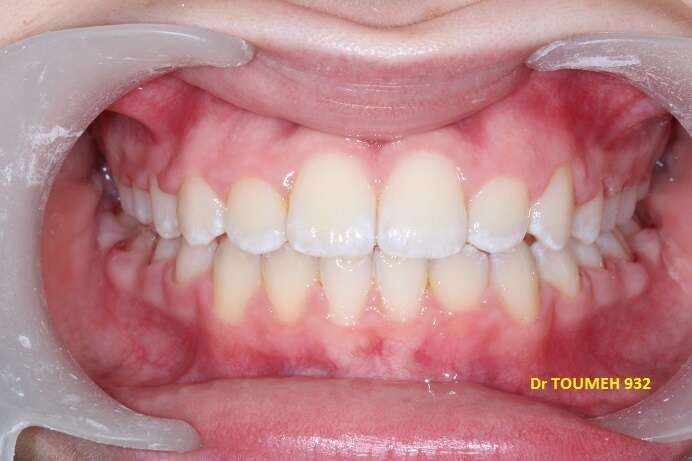

Avant

Après